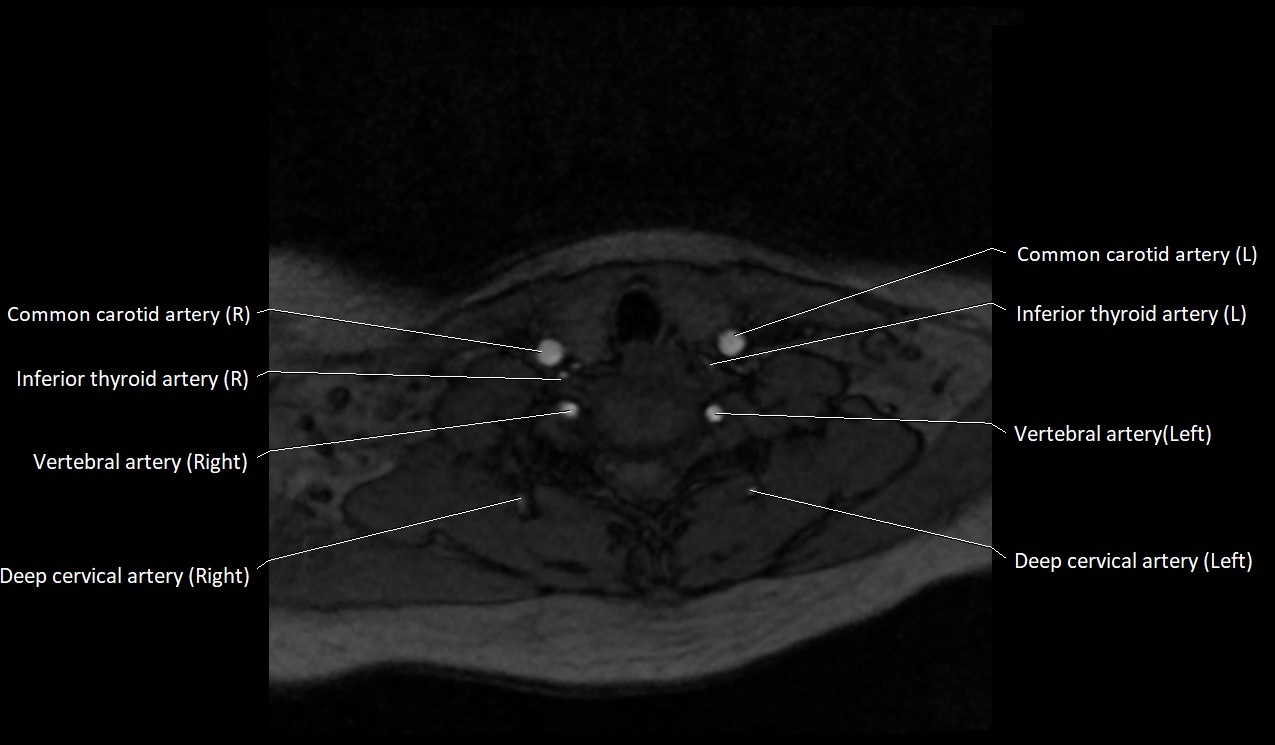

MRI Appearance:

• T1-Weighted Images:

• Appears as a tubular, hypointense (dark) structure relative to muscle

• May show flow void if the blood flow is fast

• T2-Weighted Images:

• Typically hypointense or isointense to muscle, but can be hyperintense if slow flow or stasis is present

MRI images

image